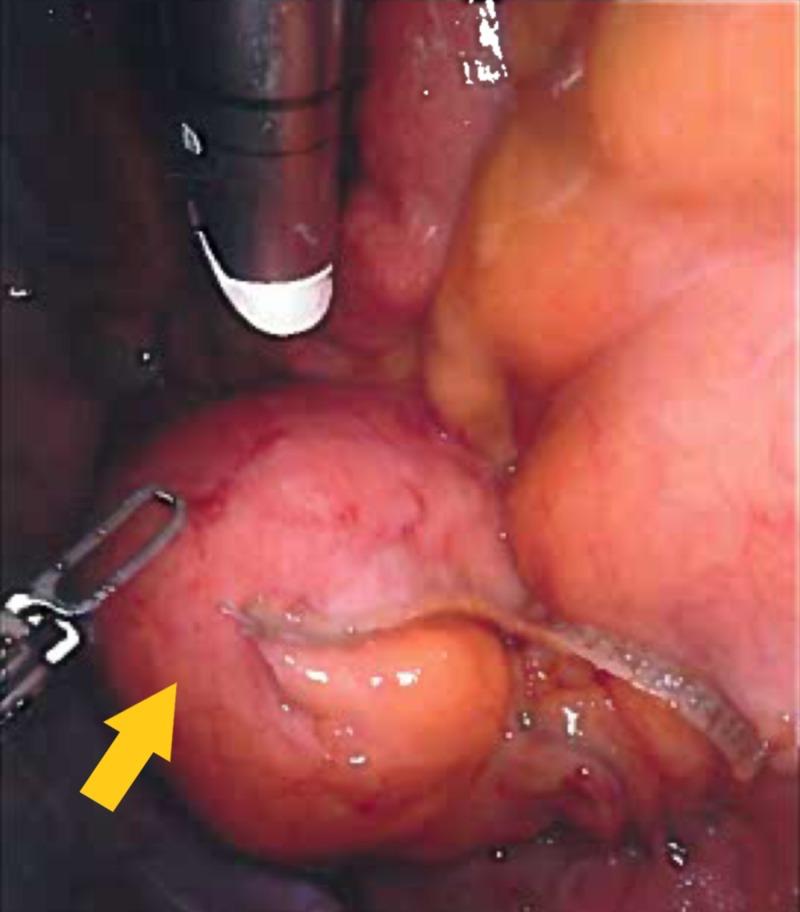

A rare case of a jejunal mesenteric pseudocyst treated by robotic resection is reported. A 25-year-old woman was admitted to our hospital with intermittent abdominal discomfort which was exacerbated by strenuous physical activities. Physical examination revealed a fluctuant mass without tenderness. Contrast-enhanced computed tomography revealed a 4 cm-sized non-enhancing heterogeneous mass on a proximal small bowel loop mesentery. Based on the findings, a differential diagnosis of a gastrointestinal stromal tumor, hematoma, desmoid tumor, and mesenteric cyst was made. Robotic diagnostic laparoscopy was performed to obtain an accurate diagnosis and treatment. Exploration of the cavity revealed a 4 cm fairly mobile mass originating from the mesentery of the jejunum. Segmental resection of the jejunum and its mesentery, including the mass and extracorporeal anastomosis, was performed without any complications. Macroscopically, the mass was cystic and the lumen had grumous material. The final pathological diagnosis was a mesenteric pseudocyst. The patient had an uneventful postoperative course.

报道了一例采用机器人切除术治疗空肠系膜假性囊肿的罕见病例。一名25岁女性因间歇性腹部不适入院,剧烈体育活动会使不适加剧。体格检查发现一个有波动感的肿块,无压痛。增强计算机断层扫描显示在近端小肠袢系膜上有一个4厘米大小的无强化的不均匀肿块。根据这些发现,对胃肠道间质瘤、血肿、硬纤维瘤和肠系膜囊肿进行了鉴别诊断。进行了机器人诊断性腹腔镜检查以获得准确的诊断和治疗。探查腹腔发现一个4厘米大小、相当活动的肿块,起源于空肠系膜。对空肠及其系膜进行了节段性切除,包括肿块和体外吻合,未出现任何并发症。肉眼可见,肿块为囊性,腔内有凝块状物质。最终病理诊断为肠系膜假性囊肿。患者术后恢复顺利。